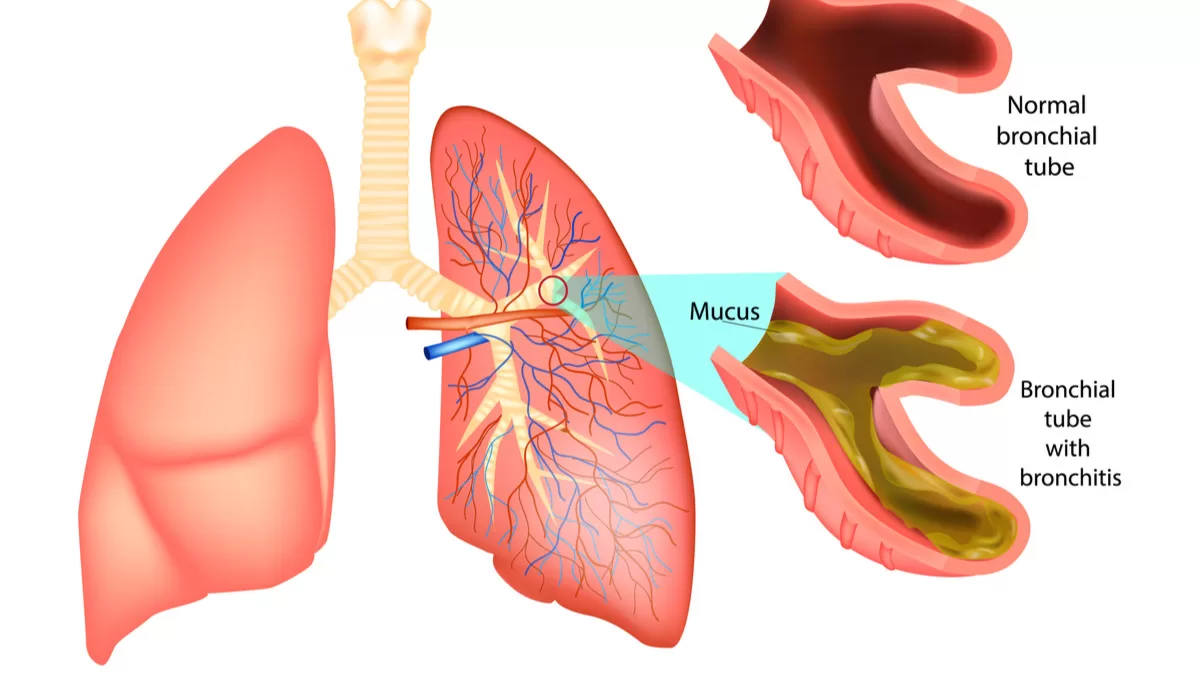

4. Bronkitis

Bronkitis adalah penyakit karena peradangan pada bronkus. Penyebabnya bisa karena infeksi kuman, bakteri atau virus. Penyabab lainnya adalah asap rokok, debu, atau polutan udara.